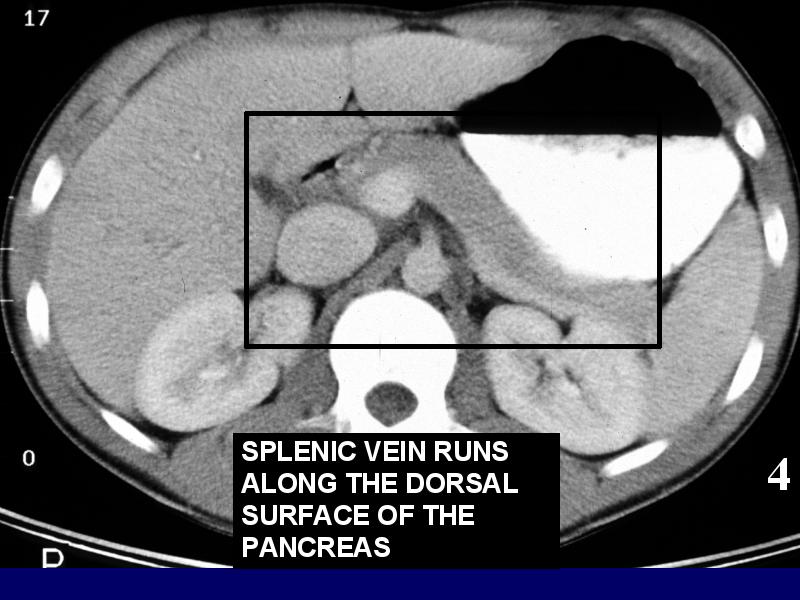

MS 190 CT 15